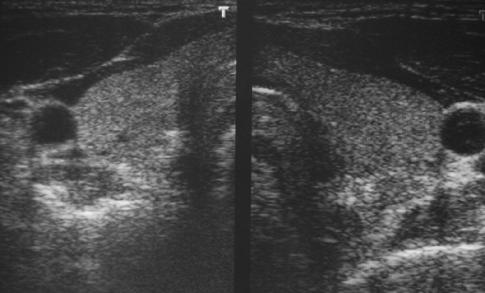

Schilddrüsensonografie

Die Schilddrüsensonografie ermöglicht

die Größenbestimmung der Schilddrüse.

Es lassen sich Schilddrüsenknoten und Zysten

(Flüssigkeitsblasen imGewebe) gut darstellen

Desweiteren kann die Strukturanalyse Hinweise auf

bestimmte Schilddrüsenerkankungen geben. z.B

auf einen M. Basedow.